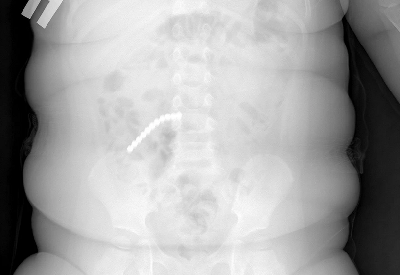

Двухлетний ребенок поступил в больницу с сильной рвотой и вялостью. Сначала родители думали - отравление или вирус. Но когда сделали рентген, врачи увидели страшное. Почти весь кишечник был усеян мелкими шариками. Как выяснилось, пациент проглотил 20 шариков от магнитного конструктора - неокуба.Девять деталей врачам удалось достать через эндоскоп. Но основная проблема была впереди. Остальные магниты разошлись по кишечнику и начали притягиваться друг к другу через стенки кишок. Из-за этого петли тонкой, слепой и сигмовидной кишки буквально слиплись между собой. Началось воспаление, образовались дырки - перфорации.

- Магниты спрессовали кишки, возникли свищи. Часть шариков даже попала в аппендикс. Пришлось удалять и его тоже, - рассказал хирург Вячеслав Данчинов.

Ребенка пришлось экстренно оперировать. Хирурги убрали поврежденный участок тонкой кишки, ушили свищи. Операция была сложной, малыш несколько дней провел в реанимации. Сейчас его уже перевели в обычную палату - идет на поправку.